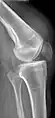

Quadriceps tendon rupture in plain X-ray

X-ray of a tear of the patellar tendon. On the left: The kneecap is pulled up. On the right: Significant dent in the soft tissue above the kneecap.